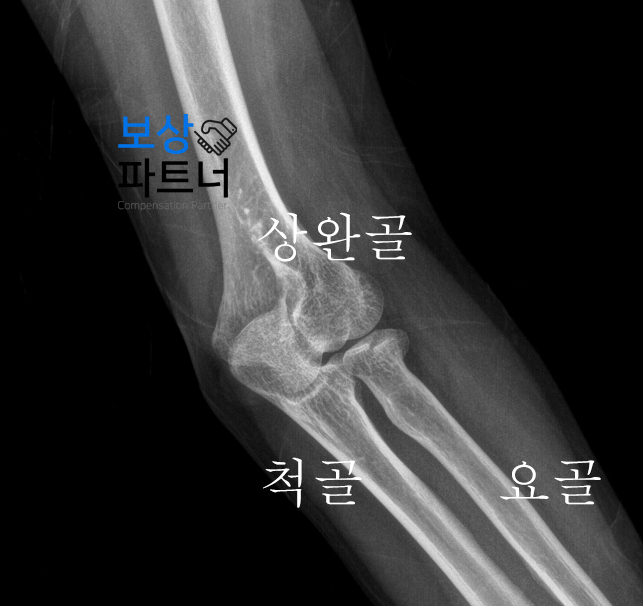

진단명(2) :

요골 머리의 골절 뿐만 아니라 팔꿈치를 구성하는 3가지 뼈 중 "요골"의 머리부분도 골절되었습니다. 팔꿈치 관절과 가까운 부위였기에 보존치료가 불가능한 상황이셨는데요. 결국 핀으로 골절부위를 정복하는 '관혈적 정복 및 내고정술'을 시행 받으셔야 했습니다.

치료방법 :

요추2번 압박골절 - TLSO보조기 착용 요골 머리의 골절 - 관혈적 정복술 피해자께서는 치료를 받으시면서 상해후유장해 보상에 대해 알아보시던 중, 인천 지역에서 손해사정 업체를 찾으셨는데요.